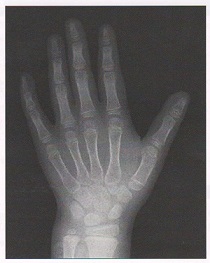

- 過成長・骨年齢促進で発見されることがある(甲状腺ホルモンが骨などの新陳代謝を活発にすると同時に、成長ホルモン分泌をうながすため)